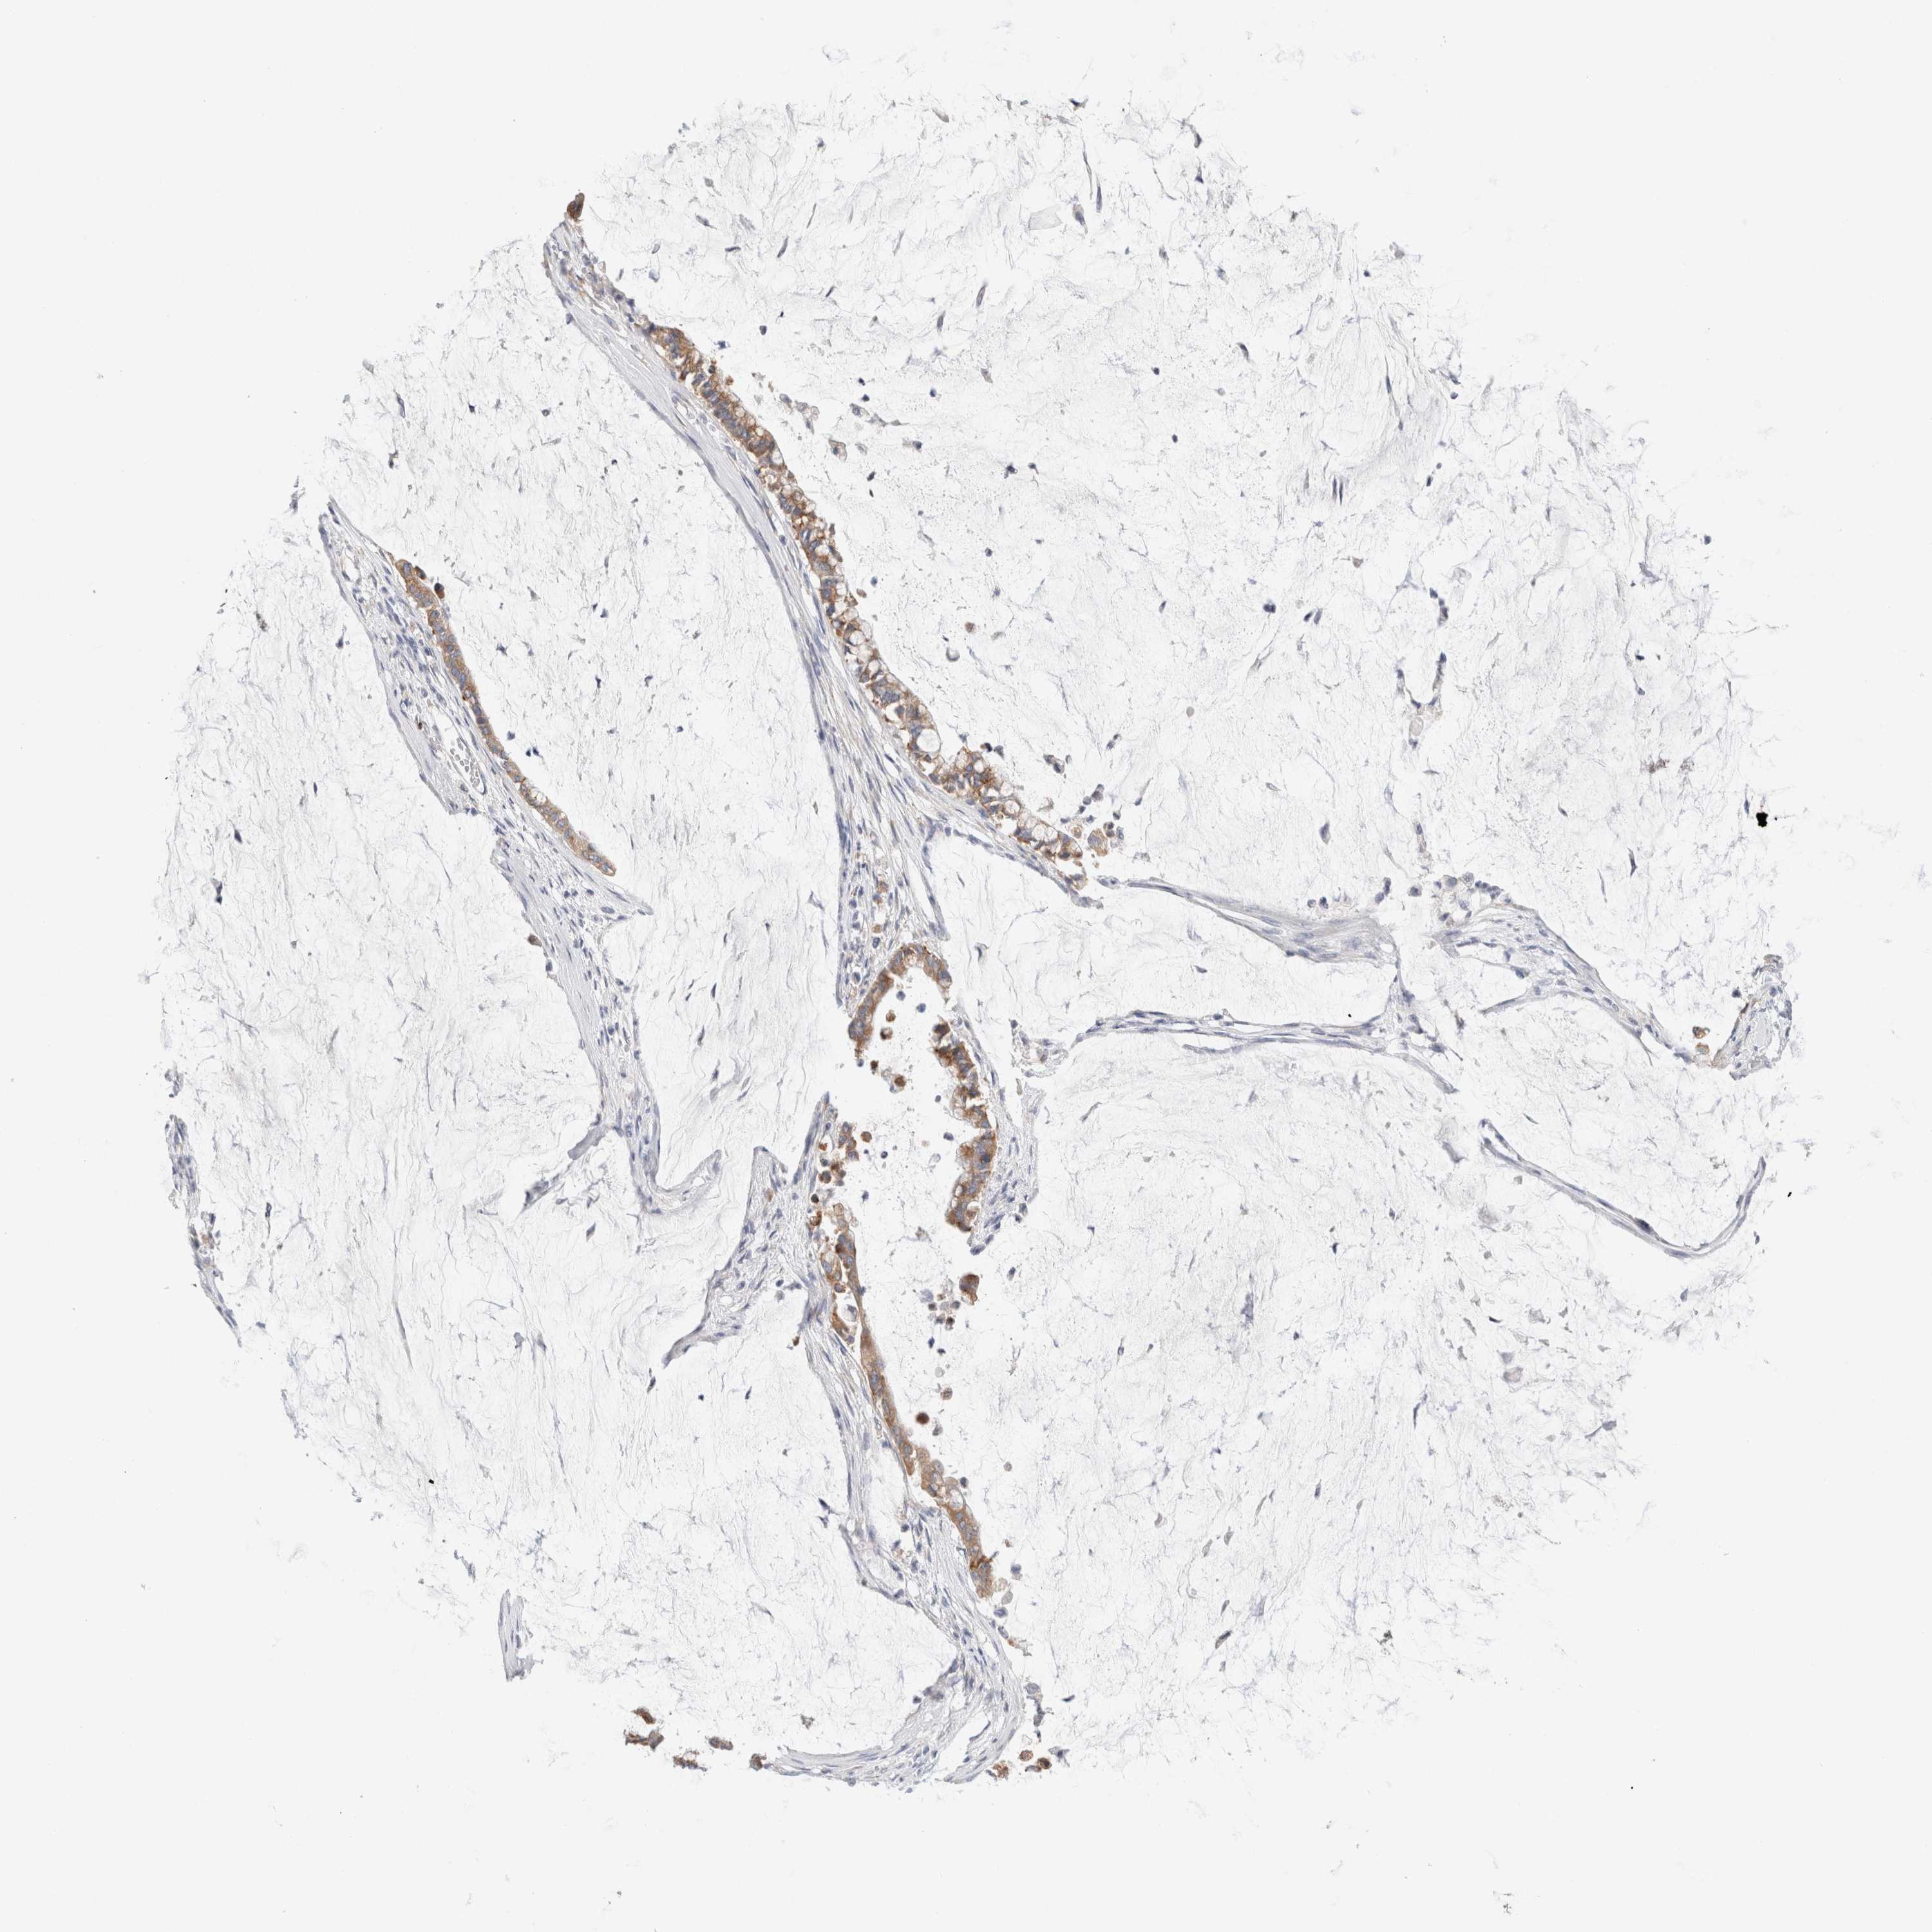

PANCREATIC CANCER - Protein expressioni

A mouse-over function shows sample information and annotation data. Click on an image to view it in a full screen mode. Samples can be filtered based on level of antibody staining by selecting one or several of the following categories: high, medium, low and not detected. The assay and annotation is described here.

Note that samples used for immunohistochemistry by the Human Protein Atlas do not correspond to samples in the TCGA dataset.

Antibody stainingi

Antibody staining in the annotated cell types in the current human tissue is reported as not detected, low, medium, or high, based on conventional immunohistochemistry profiling in selected tissues. This score is based on the combination of the staining intensity and fraction of stained cells.

Each image is clickable and will lead to virtual microscopy that enables deeper exploration of all samples and also displays staining intensity scores, fraction scores and subcellular localization as well as patient and tissue information for each sample.

Antibody HPA026488

Antibody HPA028425

Antibody CAB011203

Staining

High

Medium

Low

Not detected

Intensity

Strong

Moderate

Weak

Negative

Quantity

>75%

75%-25%

<25%

None

Location

Nuclear

Cytoplasmic/membranous

Cytoplasmic/membranous,nuclear

Adenocarcinoma, NOS

Adenocarcinoma, metastatic, NOS